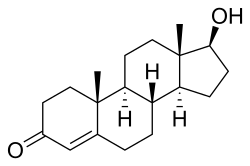

Chemical structure of the natural AAS testosterone (androst-4-en-17β-ol-3-one). | |

Anabolic steroids, also known as anabolic-androgenic steroids (AAS), are a class of drugs that are structurally related to testosterone, the main male sex hormone, and produce effects by binding to the androgen receptor. Anabolic steroids have a number of medical uses,[1] but are also used by athletes to increase muscle size, strength, and performance.

Chemistry

AAS are androstane or estrane steroids. They include testosterone (androst-4-en-17β-ol-3-one) and derivatives with various structural modifications such as:[73][186][68]